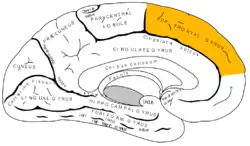

Coronal section through anterior cornua of lateral ventricles. Superior frontal gyrus is shown as yellow. | |

Lateral surface of left cerebral hemisphere Medial surface of left cerebral hemisphere

Medial surface of left cerebral hemisphere Cerebrum. Lateral view. Deep dissection. Superior frontal gyrus labelled at top-left.